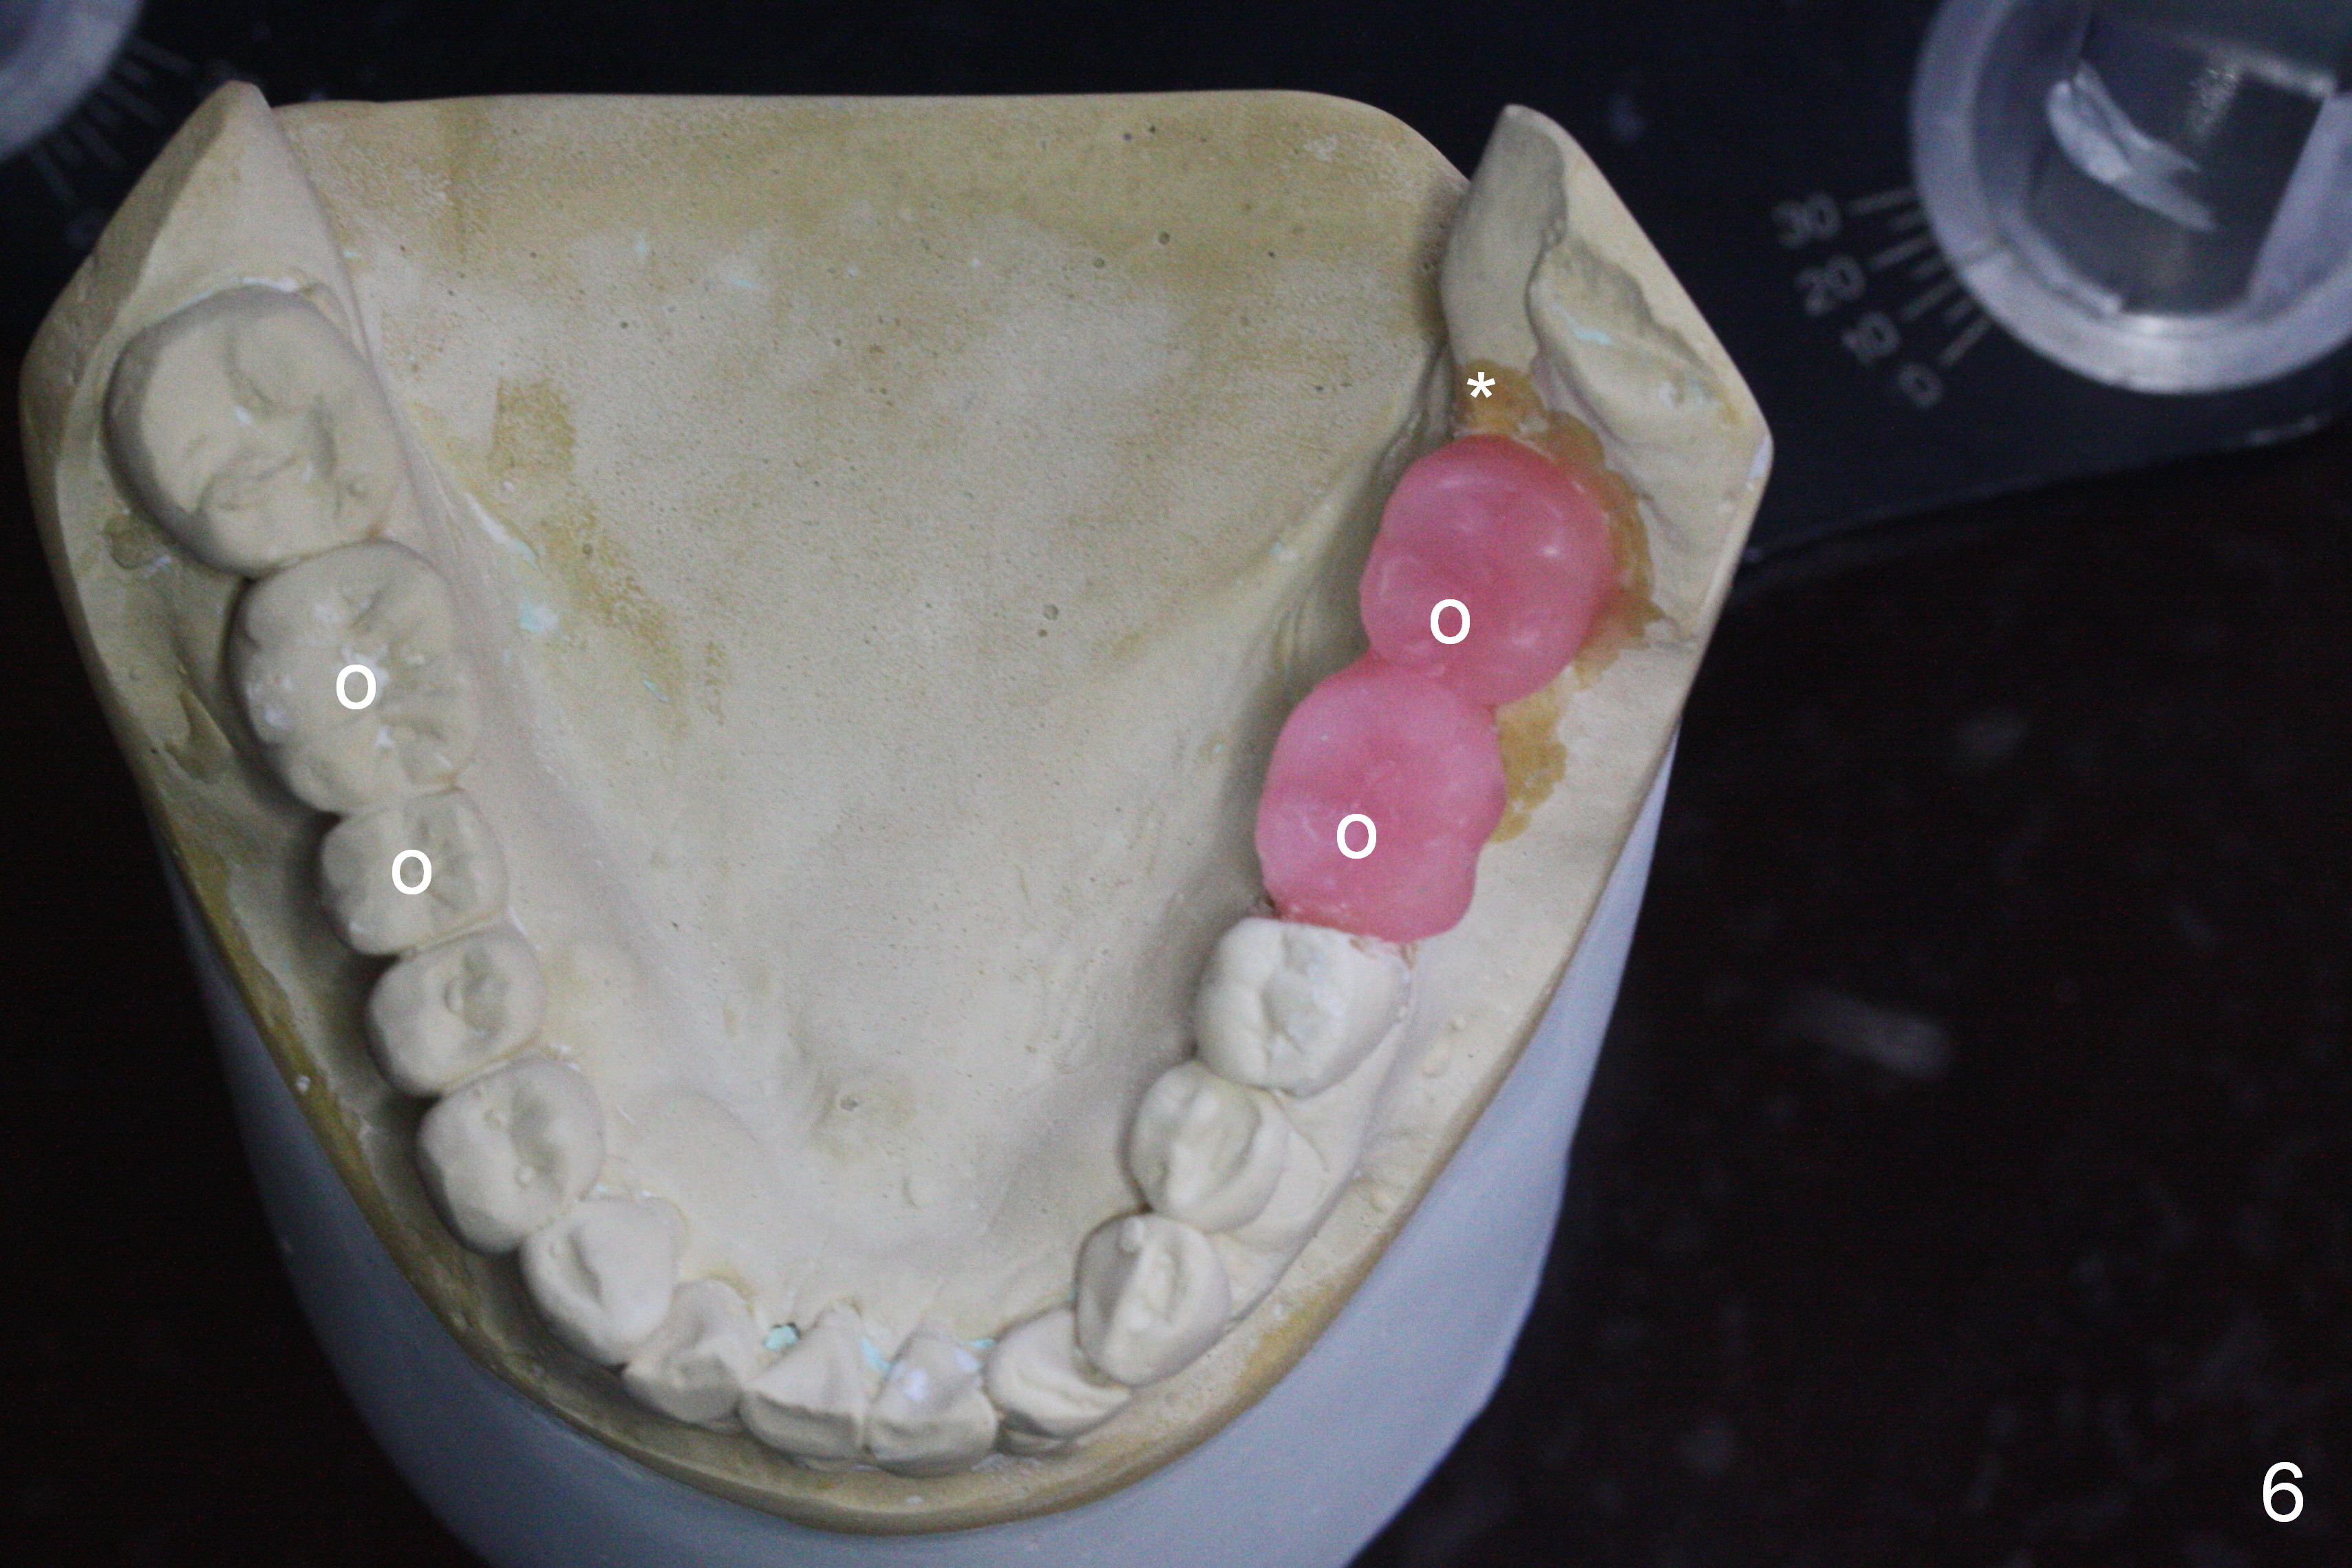

A 73-year-old woman requests implant restoration at #18 and 19 (Fig.1). The left posterior occlusion is Class II (Fig.1,2). The right one is Class I because of small dimension of the restoration at #30 (Fig.3 (premolar)). The normal size of the lower left molars will keep Class II occlusion (Fig.4), which may create cheek bite posteriorly. To correct the occlusion to Class I, move osteotomies to the mesial aspect of waxed-up molars (Fig.6 white circles). Finally a premolar crown and the 1st molar will be placed at #19 and 18, respectively. The supraerupted opposing molars (Fig.5 arrowheads) will to be adjusted when the abutments are placed at the lower molars.